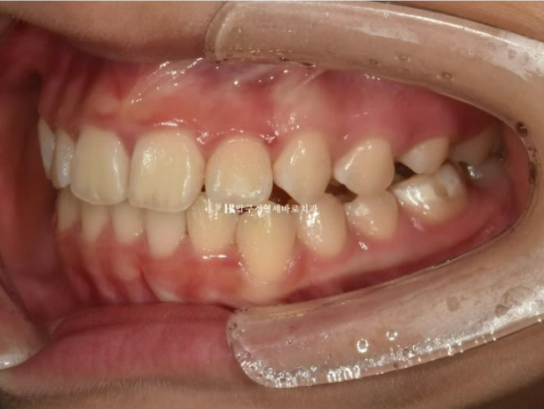

오른쪽 교합은 나쁘지 않습니다.

23.08

왼쪽은 3급 교합관계 때문에 왼쪽 어금니는 잘 안 물리고 이것이 앞니에 영향을 주어 위 앞니 중심이 인중과 얼굴에 비하여 틀어져 있습니다.